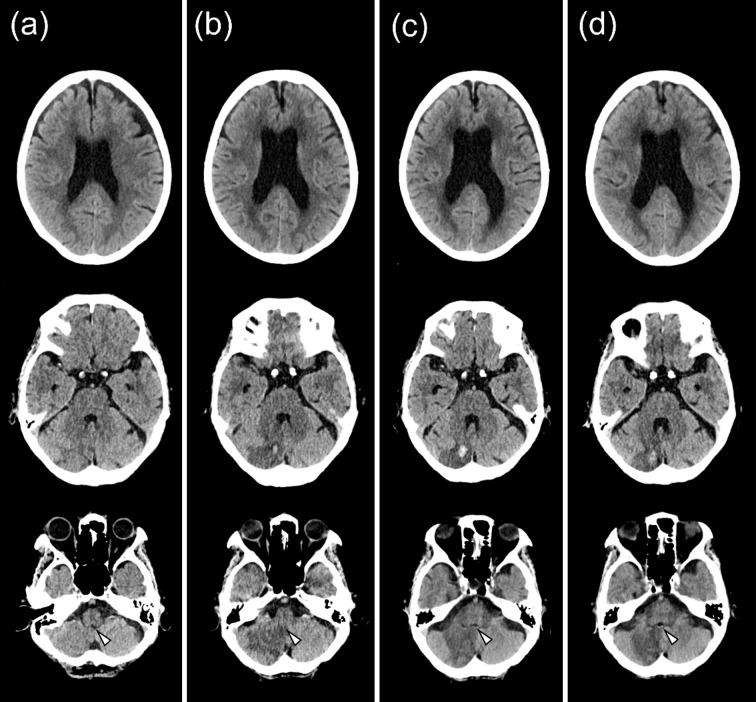

An 80-year-old woman presented with the sudden onset of vertigo and vomiting and was diagnosed with acute cerebellar infarction. Twelve days after the onset, she experienced positional vomiting, predominantly in the lying-down position, triggered by postural changes with immediate or delayed onset. Over 1 month, 23 episodes of vomiting occurred. Brain computed tomography revealed edema in the infarcted area, fourth ventricular outlet compression, and lateral ventricular enlargement. These findings suggest that fluctuations in intracranial pressure are associated with intermittent obstructive hydrocephalus exacerbated by the patient's posture. This case highlights the importance of considering postural triggers in patients with recurrent vomiting associated with cerebellar infarctions.

一位80岁的妇女表现为突然发作的眩晕和呕吐,并被诊断为急性小脑梗死。发病12天后,患者出现体位性呕吐,主要发生在平卧位,由体位变化引发,即刻或延迟发作。1个月内,呕吐发作23次。脑ct显示梗死区水肿,第四脑室出口受压,侧脑室增大。这些发现表明,颅内压波动与间歇性阻塞性脑积水有关,患者的姿势加剧了脑积水。本病例强调了考虑小脑梗死患者复发性呕吐的体位触发因素的重要性。